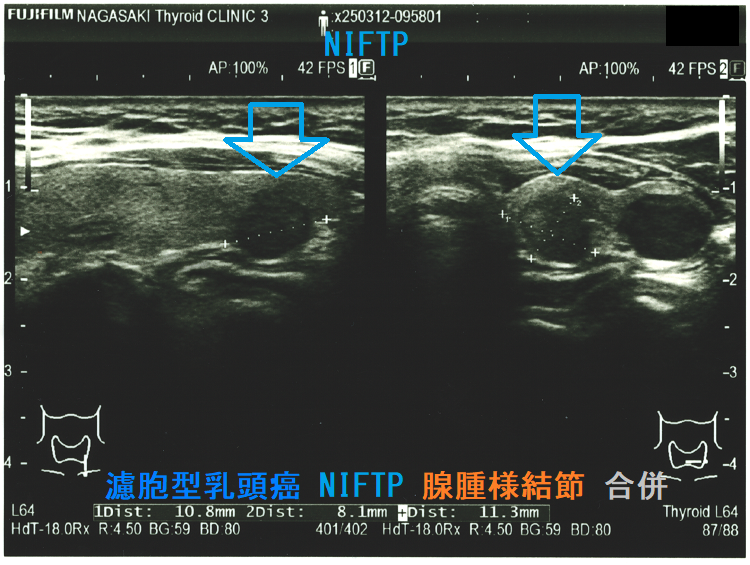

Non-invasive follicular thyroid neoplasm with papillary-like nuclear features (NIFTP) 超音波(エコー)画像 (水平断)

Non-invasive follicular thyroid neoplasm with papillary-like nuclear features (NIFTP) 超音波(エコー)画像;見かけは濾胞型甲状腺乳頭癌、濾胞性腫瘍と鑑別できまない

Non-invasive follicular thyroid neoplasm with papillary-like nuclear features (NIFTP)の超音波(エコー)所見は、

- 被膜が存在(被膜のない場合もある)

- 充実性、等エコーが多い

- 砂粒状石灰化を認めない

などで、濾胞型甲状腺乳頭癌、濾胞性腫瘍(良性濾胞腺腫 、甲状腺濾胞癌)と鑑別できません。砂粒状石灰化のない濾胞型甲状腺乳頭癌なんて普通に存在します。NIFTPの60.1%は悪性を疑う所見が無いとされます[Endocrine. 2021 Jul;73(1):131-140.]。